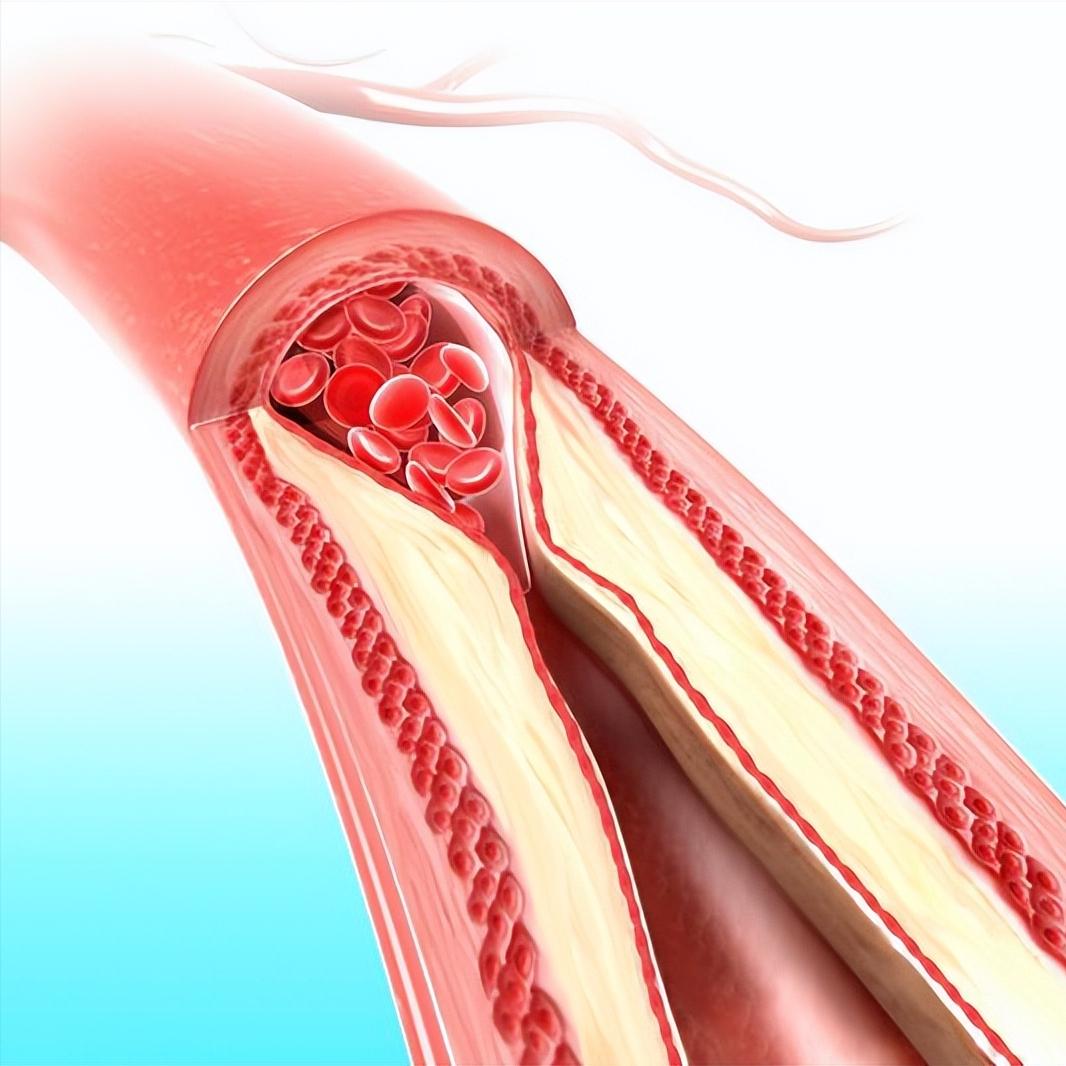

房颤患者突发肢体乏力要警惕脑卒中!昨天上夜班就碰到这样一例患者。这是一位49岁女性患者,因为风湿性心脏病心衰住院。住院以后用了抗凝药物预防脑梗,同时也用了一些心衰相关的药物。晚上9点钟左右,突然发现左手和左腿乏力,抬不起来。赶到床边看患者,发现左手的肌力大概在一级左右,右侧肢体肌力正常。这是很典型的急性脑梗的表现,立马让值班医生带患者去去急诊CT室做急诊的脑动脉CTA。 结果显示右侧大脑中动脉闭塞,这是心房颤动时,心房内的血栓随血液游走至大脑中动脉,无法通过,就堵塞了血管。紧急联系神经内科,做了急诊取栓手术,取出了一块血栓。 心房颤动(房颤)时心房没有了收缩功能,心房内血液容易淤积形成血栓,血栓随着血液流动到全身。引起一些脏器的栓塞症状。比如,栓塞了脑血管就会引起脑梗塞、偏瘫等症状。栓塞了肠系膜动脉,就会引起腹痛等症状。栓塞了脾动脉就会引起脾梗塞。所以房颤的治疗,最重要的就是预防脑梗塞等脏器栓塞并发症。方法就是口服抗凝药物,比如利伐沙班,艾多沙班,达比加群酯等等。 房颤治疗方法 房颤预防